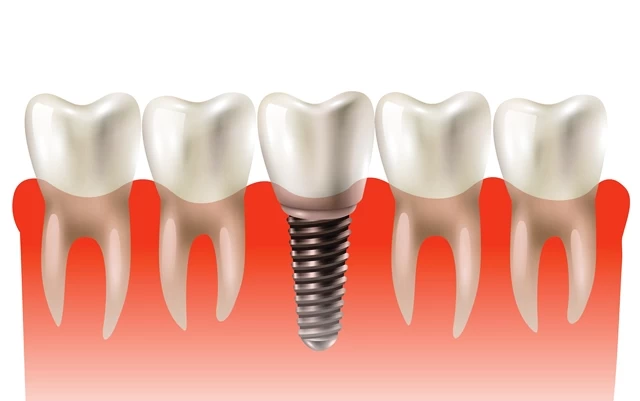

Diş implantları, diş köklerinin yapay olarak oluşturulduğu ve çene kemiğine yerleştirildiği kalıcı diş tedavisi yöntemidir. Bir implant, titanyumdan yapılmış bir vida şeklindedir ve çene kemiği içine yerleştirilir. İmplantın yerleştirilmesi sürecinde lokal anestezi uygulanır ve cerrahi bir işlem gerektirir. İmplantlar, doğal dişlere benzer şekilde hareket edebilen ve fonksiyon görebilen yapay diş kökleri olarak çalışır. İmplantlar üzerine yerleştirilen porselen kaplamalar, doğal dişleri taklit eden estetik bir görünüm sağlar.

- İmplant Yerleştirme: İmplant yerleştirme işlemi, lokal anestezi altında gerçekleştirilir. Diş hekimi, çene kemiğine küçük bir kesi yapar ve implantı doğru konumuna yerleştirir. İmplant, çene kemiğiyle birleşene kadar iyileşme sürecine alınır.

- Porselen Kaplama Uygulaması: İmplantın iyileşmesinin tamamlanmasının ardından, kalıcı porselen kaplama veya protezler yerleştirilir. Bu aşamada, implantın şekli ve boyutu ölçülerek, kişiye özel bir kaplama veya protez yapılır.